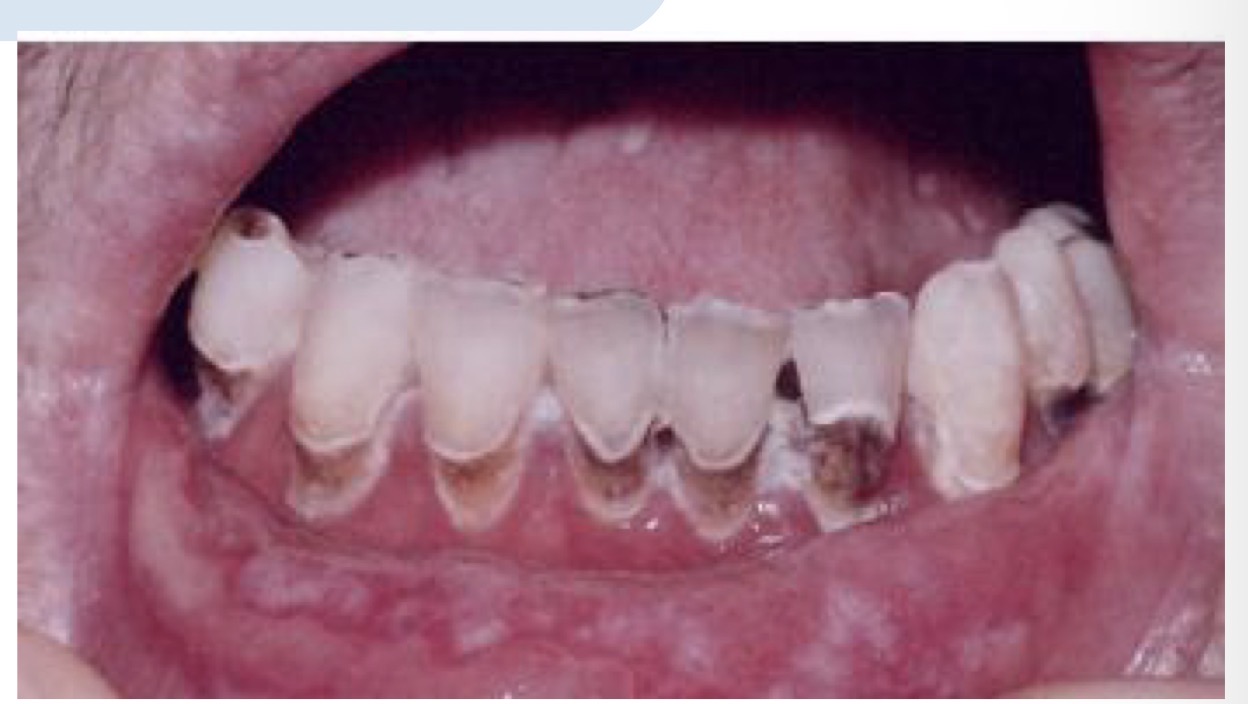

CHẨN ĐOÁN ?

SÂU RĂNG SAU XẠ TRỊ( sâu nhiều răng và lang quanh cổ răng)